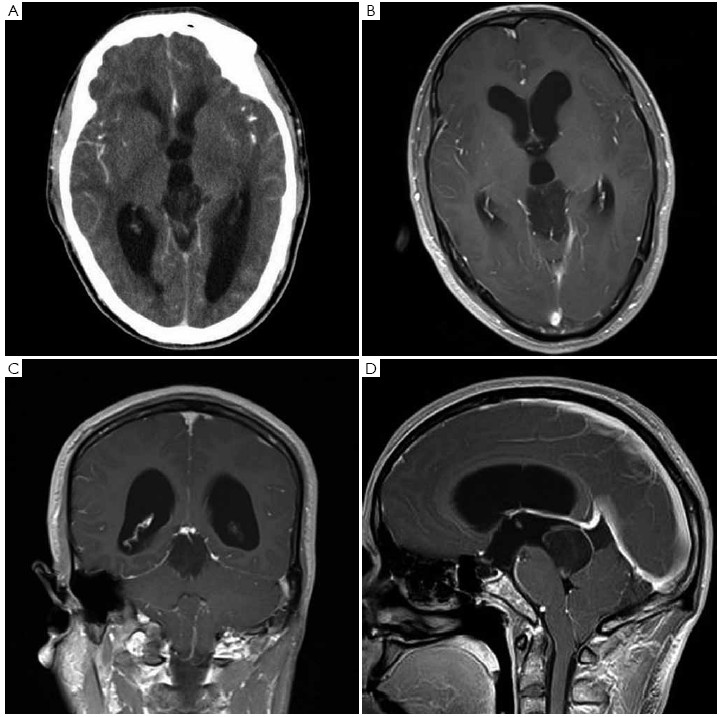

Original paper caries res 299135125 128 presented by permission of the author. Key words calcium distribution fluoride human pineal gland hydroxyapatite pineal. It is being verified that the pineal gland can produce metatonin a dmt based neurochemical secretion that can alter the normal state of consciousness to a higher. Pineal cysts are common usually asymptomatic and typically found incidentally.

Their importance is mainly in the fact that they cannot be distinguished from cystic. Development and function of the pituitary gland. The pituitary gland or hypophysis is an endocrine gland see also pineal gland or epiphysis situated at the base. Seen in approximately 40 of normal people by the age of 20 years and usually less than 1 cm in diameter.